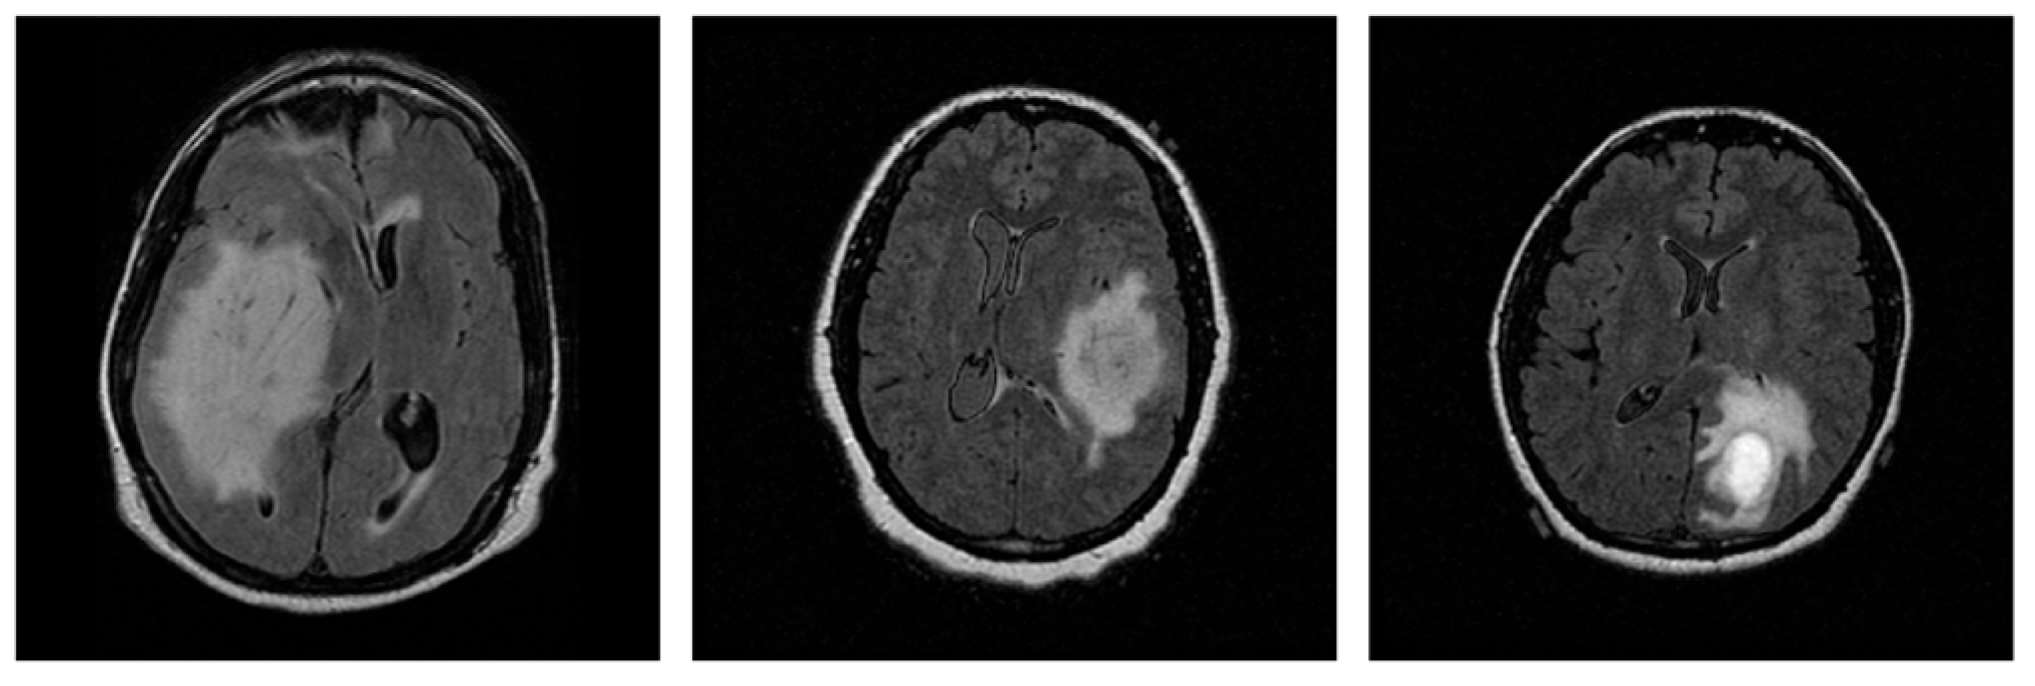

2.1. Data Collection

2.2. Data Pre-Processing